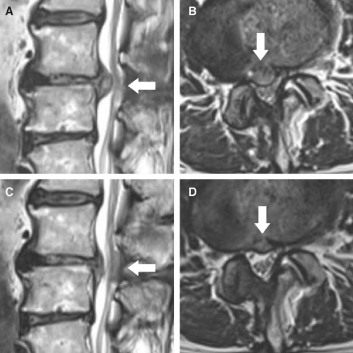

전세계적으로 널리 시행되고 있는 치료법으로 많은 연구를 통해 효과가 입증된 치료법 입니다. 내시경을 이용하여 척추관 및 경막외강을 직접 육안으로 관찰하고 통증의 원인을 찾아 치료하는 시술법 입니다. 실시간 영상장치인 C-arm과 내시경을 동시에 사용하여 시술의 안전도와 정확도를 높입니다.

꼬리뼈를 통해 내시경 카메라를 장착한 특수 카테터를 삽입하여 협착 부위의 디스크 및 신경을 확인 합니다. 필요에 따라 유착과 염증을 제거하고 레이저 시술을 통해 디스크의 사이즈를 줄입니다. 국소마취만으로 진행 되며 전신 마취가 필요 없어 시술 후 회복이 빠릅니다.